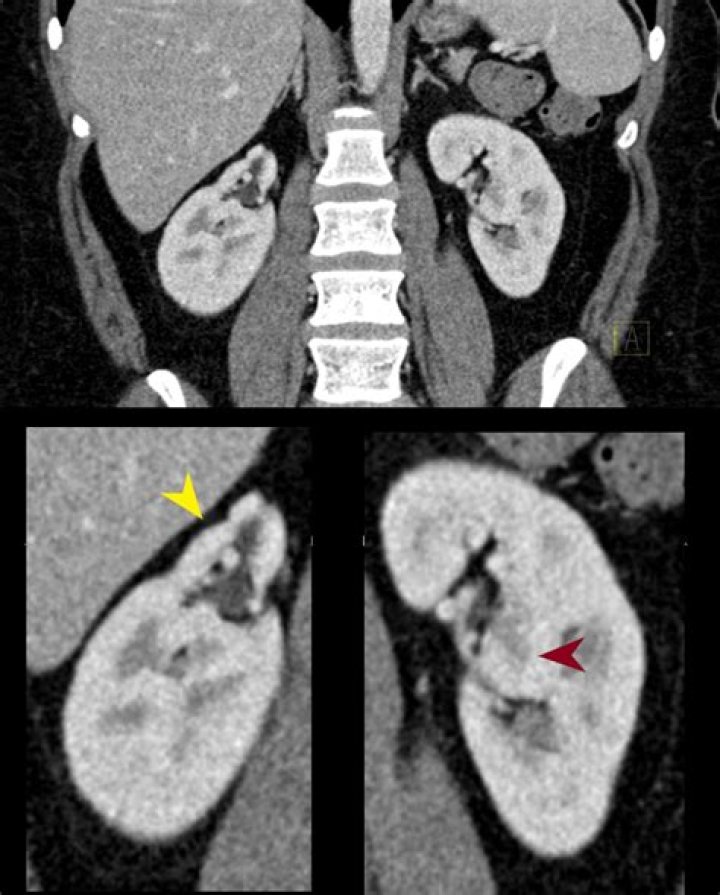

Columns of Bertin represent the extension of renal cortical tissue which separates the pyramids, and as such are normal structures. They become of radiographic importance when they are unusually enlarged and may be mistaken for a renal mass (renal pseudotumor).Click to see full answer. Similarly, it is asked, what causes hypertrophied column of Bertin?A hypertrophied column of Bertin is one of the congenital causes of renal pseudo tumor. The columns of Bertin are normal structures seen in the renal cortical tissue. Hypertrophied columns of Bertin are actually not hypertrophic but they occur due to an incomplete fusion of the fetal lobes.Beside above, what vessel is found within the renal column? Nephrons and Vessels The renal artery first divides into segmental arteries, followed by further branching to form interlobar arteries that pass through the renal columns to reach the cortex. The interlobar arteries, in turn, branch into arcuate arteries, cortical radiate arteries, and then into afferent arterioles. Then, what is Bertin? The renal column (or Bertin column, or column of Bertin) is a medullary extension of the renal cortex in between the renal pyramids. It allows the cortex to be better anchored. Each column consists of lines of blood vessels and urinary tubes and a fibrous material.Where are columns of Bertini located?Columns of Bertin are found in kidney. It is the extension of renal cortex in between the renal pyramid. It allows the better anchoring of renal cortex. It consists of lines of blood vessels and urinary tubes and a fibrous material.